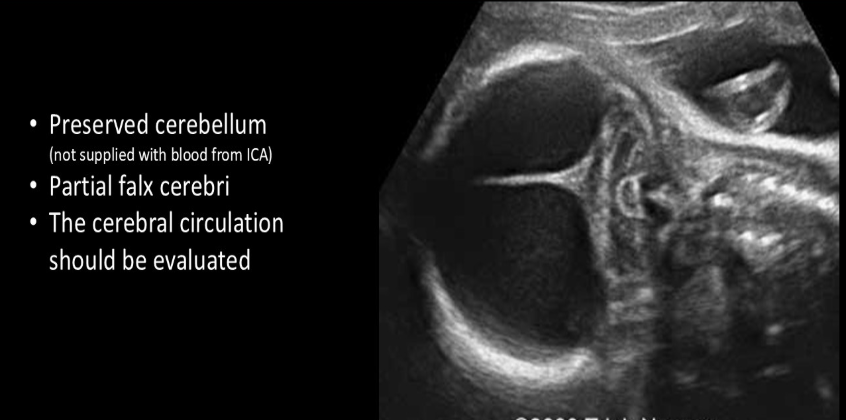

holoprosencephaly is commonly assoc w

a) noonan

b) trisomy 13

c) turner

d) trisomy 21

a midline facial cleft is most commonly assoc w/what intracranial abn

a) hydranencephaly

b) dandy walker malformation

c) hydrocephalus

d) holoprosencephaly